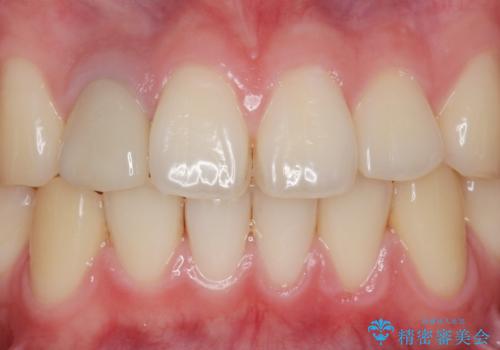

失活(神経が死んでしまっていること)により黒くなった歯根が透けて歯ぐきも黒ずんで見えるため、歯肉移植の手術も提案しましたが、そこまでは気にならないとご希望されませんでした。

自然な仕上がりにご満足頂けました。

当院では、できあがったクラウンを試適した状態でご確認頂き、必要があれば色や形態を修正したり、ご希望があれば仮付けをして1~2週間様子を見て頂いたりすることが可能です。(処置内容はクラウンのグレードにより変わります)

治療終了時には「修正や仮付けをしてもらえて納得のいく治療を受けられました。この病院にして良かったです!」とおっしゃって下さいました。